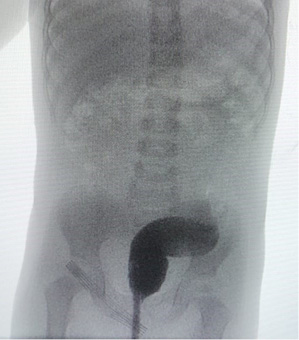

Выполнено инструментальное обследование: ретроградное рентгеноконтрастное исследование нижних отделов толстой кишки (ирригография) (рис. 1), магнитно-резонансная томография (МРТ) крестцово-копчиковой области (рис. 2), в ходе которого на основании клинической картины (хронического толстокишечного стаза), наличия аномалий строения анального канала (стеноз), а также выявленных аномалий дистальных отделов позвоночника установлен диагноз: врожденный стеноз анального канала в составе синдрома Куррарино, осложненное хроническим толстокишечным стазом, мегаректум.

Рисунок 1.

Расширенные нижние отделы толстой кишки, праворасположенная сигма. Опорожнение не получено. Рельеф складок слизистой толстой кишки не изменен. Область анального канала сужена (ирригография)

Figure 1.

Enlarged lower colon, right-angled sigma. Emptying was not received. The relief of the folds of the colon mucosa is not changed. The anal canal area is narrowed (irrigography)